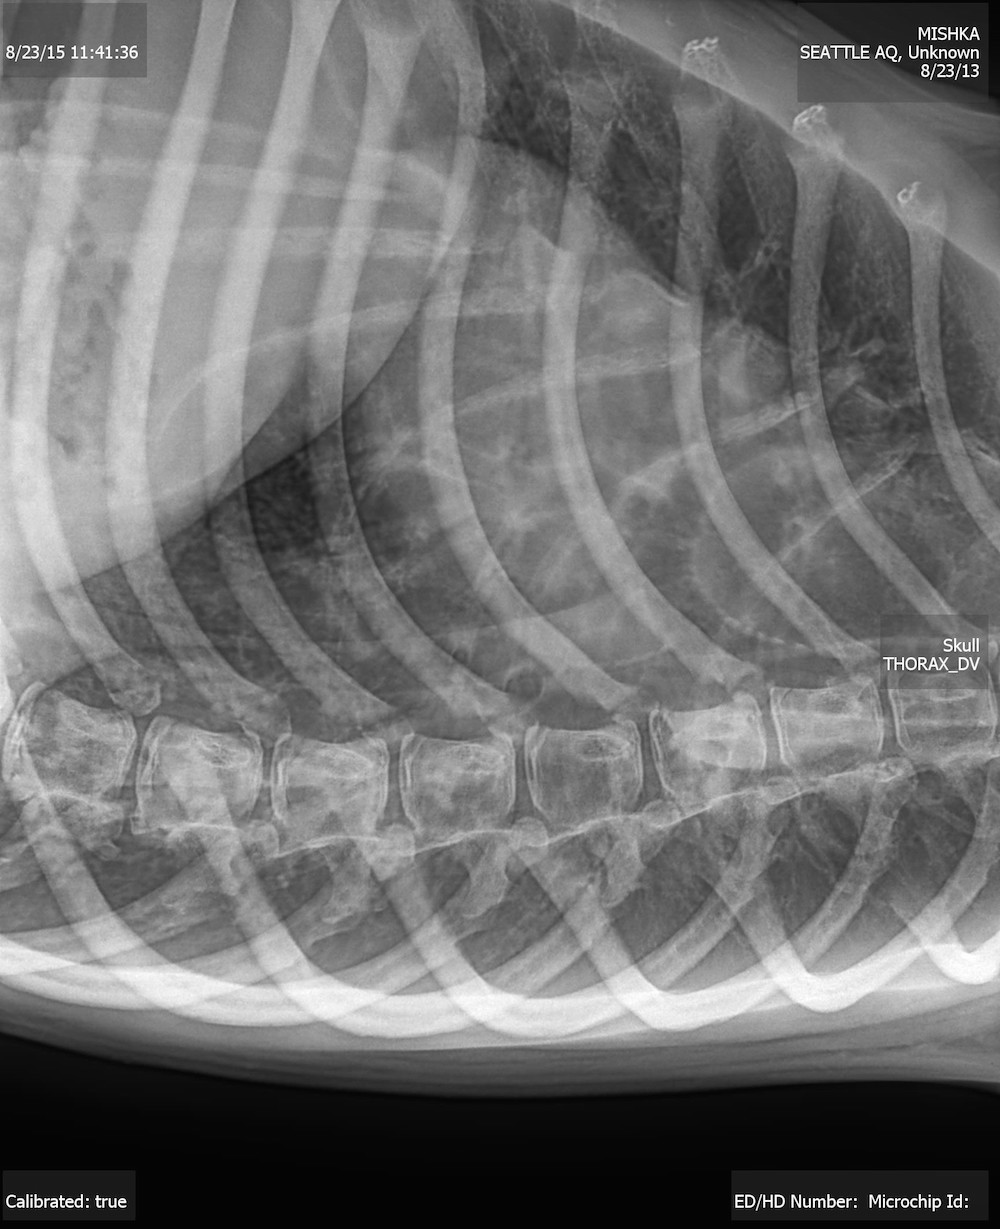

A radiograph of Mishka’s lungs showed that she has asthma.

The radiograph showed that Mishka had abnormal thickening on her bronchial walls . This can make it unmanageable for enough oxygen to enter the lungs — a pattern that " is typical of what is seen in cats presenting with acute bronchial asthma , " Lahner say .